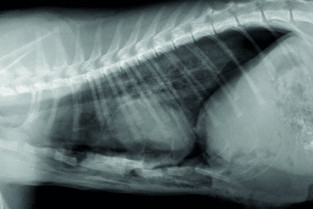

Le GEIM vous propose une séance de travaux pratiques de radiographies sur le thorax. Tous les aspects sont abordés sous la forme de TP de lecture de radiographies numériques sur station de travail Osirix sur Mac (3 vétérinaires maximum/ordinateur).

- décrire les principes à respecter pour obtenir une radiographie thoracique de bonne qualité ;

- adopter une méthodologie pour interpréter les affections de la cage thoracique, de la plèvre, et du médiastin chez les carnivores domestiques ;

- décrire l’aspect normal et anormal de la cage thoracique, de la plèvre, et du médiastin chez les carnivores domestiques.